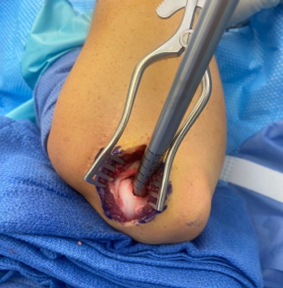

- Elbow arthroscopy is used for fragment excision, loose body removal and debridement for small unstable fragments

Arthroscopic examination of an OCD lesion

The damaged cartilage and underlying bone is removed using appropriate sizers